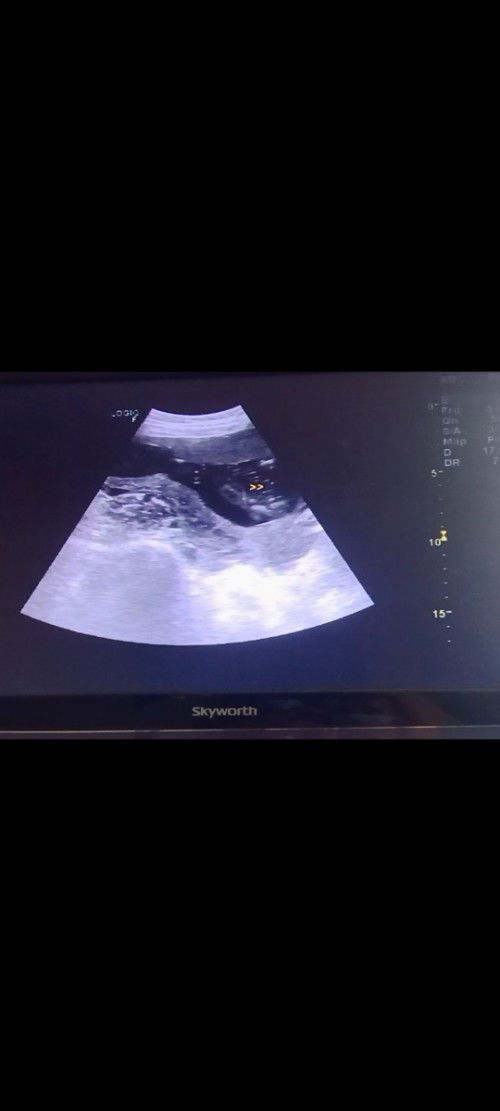

80% boy , sure na kaya ito?π

Nagpa ultrasound kami nung 18 weeks palang then ang sabi ng ob is 80% boy(yan yung nasa picture), tapos bumalik kami ng 22 weeks na nagtago naman si baby naka cross legs kaya hindi nakita.. babalik ulit kami ng june 10 for confirmation. Boy na nga kaya sya based sa picture ..super excited kasi kami.malaman.π